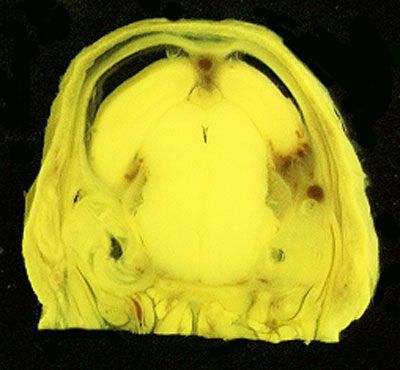

NORMAL APPEARANCE OF THE BOUIN'S FLUID FIXED RAT HEAD

The images below show the normal appearance of Bouin's fluid fixed head sections in specimens at Day 21 of gestation (day mating observed = Day 0).

It is essential that both sides of each section is examined so that structures that exist is several sections can be visualised by the examiner in 3D.

Learning objective: Compare the diagrams with your own specimens and identify all of the structures that have been labelled.

Unlabelled Images